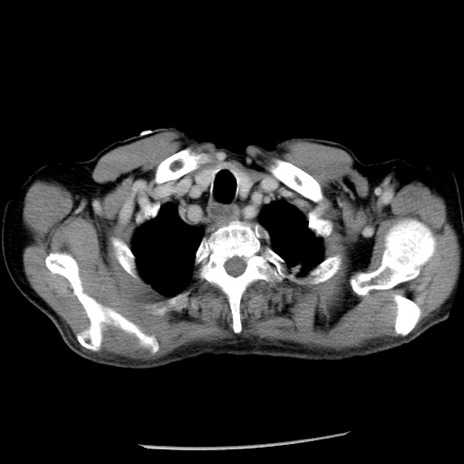

冠状断像

【症例】80歳代男性

【主訴】嘔吐

【現病歴】昨晩2回嘔吐あり、今朝になっても嘔吐あり。来院。

【既往歴】胃潰瘍

【身体所見】意識清明、BT 37.6℃、BP 166/95mmHg、HR 100bpm、SpO2 97%、腹部:平坦・軟、腸蠕動音聴取良好、圧痛なし。

【データ】WBC 21900、CRP 1.46